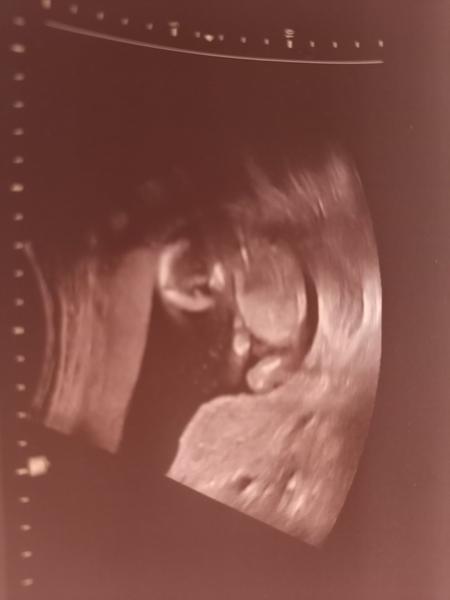

Ahoj holky,

tak dneska jsme byli na ultrazvuku v 20.tt. Bylo tam vidět tohle ...No paní doktorka nám řekla, že by zatím nedělala závěry, co to bude a že máme počkat.

Jasně, že počkáme na doktora, ale jsem strašně zvědavá. A hlavně...asi tam vidím pindíka 😁 Tak na to prosím taky koukněte, jestli jsem si to nevsugerovala 😁